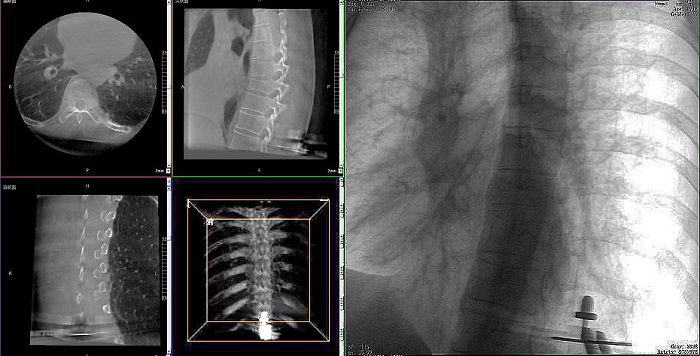

①機(jī)器人輔助胸椎手術(shù)操作難點(diǎn)之圖像采集

胸椎緊鄰肺部,患者的呼吸運(yùn)動(dòng)會(huì)造成椎節(jié)的相對(duì)移動(dòng),獲取清晰、穩(wěn)定的影像較為困難。高質(zhì)量的影像是精準(zhǔn)導(dǎo)航的重要前提,胸椎手術(shù)中,如果呼吸造成的移動(dòng)無法得到有效控制,則會(huì)降低導(dǎo)航的精度,增加手術(shù)風(fēng)險(xiǎn)。人體深吸氣胸圍與深呼氣胸圍的差值約為6~8厘米。

普愛醫(yī)療手術(shù)導(dǎo)航定位系統(tǒng)解決方案

高清三維成像:普愛醫(yī)療精研三維成像技術(shù)13年,自研的三維C形臂可為手術(shù)提供清晰、穩(wěn)定的三維圖像,為醫(yī)生精準(zhǔn)開展胸椎手術(shù)提供影像保障。

亞毫米級(jí)精度:普愛醫(yī)療三維C形臂+骨科手術(shù)機(jī)器人,基于同一技術(shù)平臺(tái)研發(fā),借助一體化自適應(yīng)配準(zhǔn)及無損圖像傳輸技術(shù),整體協(xié)同性更高,精度可達(dá)亞毫米級(jí)。

快速掃描:麻醉師通過適當(dāng)?shù)暮粑刂疲浜先SC形臂的快速掃描模式,可以在短時(shí)間內(nèi)完成圖像采集,減少因呼吸運(yùn)動(dòng)造成的圖像干擾。